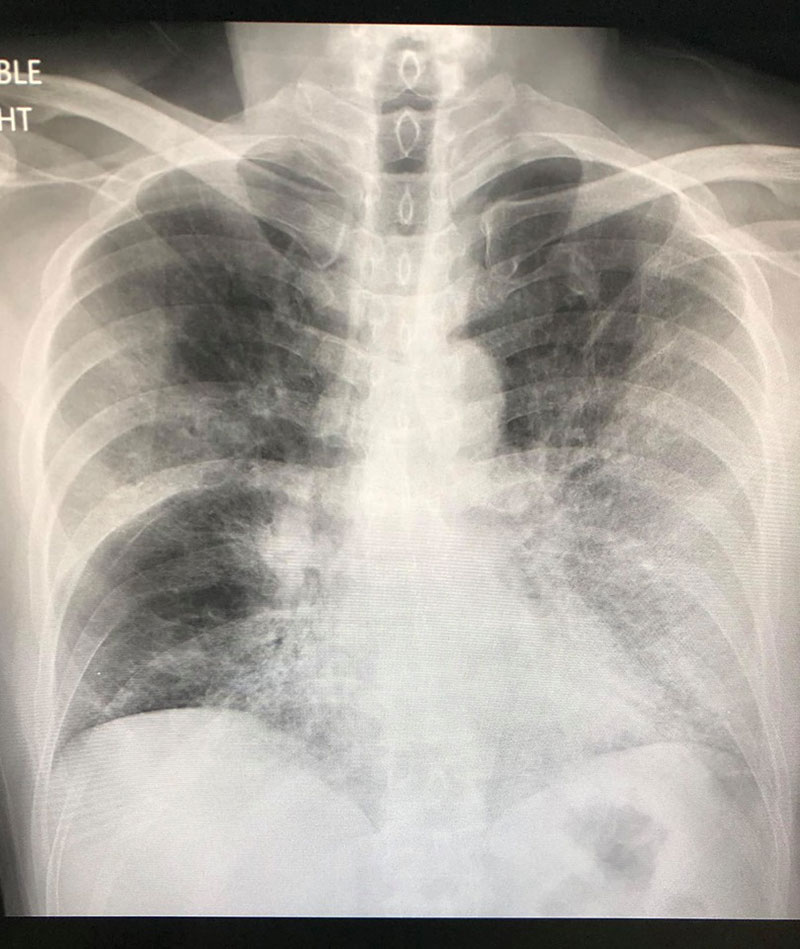

อย่างไรก็ตาม อาการของผู้ป่วยไม่ดีขึ้น ซ้ำยังต้องให้ออกซิเจนตลอดเวลา จึงทำการเอกซเรย์ปอดอีกครั้ง และพบว่า ปอดด้านซ้ายผิดปกติมากกว่าด้านขวา และปอดข้างขวารั่ว 15%

ต่อมา ชายคนดังกล่าวอาการดีขึ้นเล็กน้อย ปอดรั่วดีขึ้น แต่อาการมาแย่อีกทีในวันที่ 17 ที่นอนในโรงพยาบาล ปอดดูแย่ ต้องใส่เครื่องช่วยหายใจ และแม้จะให้ออกซิเจน 100% แล้ว ระดับออกซิเจนในเลือดยังต่ำมาก หมอจึงส่องกล้องเพื่อดูหลอดลม และเห็นตุ่มเล็ก ๆ ในหลอดลมใหญ่ด้านขวา จึงมีการดูดเสมหะและตัดชิ้นเนื้อส่งตรวจ จึงพบเชื้อราเป็นจำนวนมาก